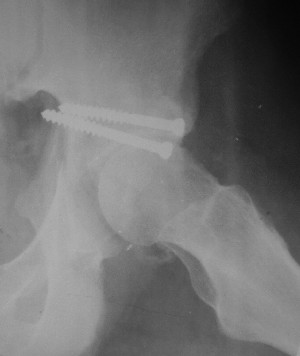

Послеоперационный снимок прямой 5/05/03

|

Больной 18 мая 2003 года в автоаварии получил перелом левой вертлужной впадины, вывих бедра. Госпитализирован в один из стационаров области.Вывих вправлен. В последствии бедро вывихивалось еще дважды. На консультацию был представлен снимок от 19.05.03г., больной переведен к нам 3.06.03г. Снимок при поступлении - перелом впадины, задне-верхний вывих бедра. 05.06.2003 г. выполнено открытое вправление вывиха левого бедра и остеосинтез стенки вертлужной впадины двумя винтами. Послеоперационный период без осложнений. Объем движений в левом тазобедренном суставе восстановился полностью. Выписан на амбулаторное лечение в удовлетворительном состоянии с рекомендациями 3 месяца ходить на костылях без нагрузки на оперированную конечность. На контрольных рентгенограммах левого тазобедренного сустава 13.10.2003 г. - признаки консолидации перелома; плотность, форма головки и состояние суставных поверхностей удовлетворительные. Разрешена дозированная осевая нагрузка, на конечность с использованием дополнительной опоры. 19.12.2003 г. больной обратился с жалобами на боли в левом тазобедренном суставе. На рентгенограммах левого тазобедренного сустава 19.12.2003 г., 20.02.04г. - асептичекий некроз головки бедра. 5.04.04г. - эндопротез. Сейчас ходит без трости, не хромает. Особенность эндопротезирования - при удалении винтов прослежена линия перелома заднего края впадины и предложено установить чашку несколько меньшего диаметра, чтобы она была покрыта несломанной частью.